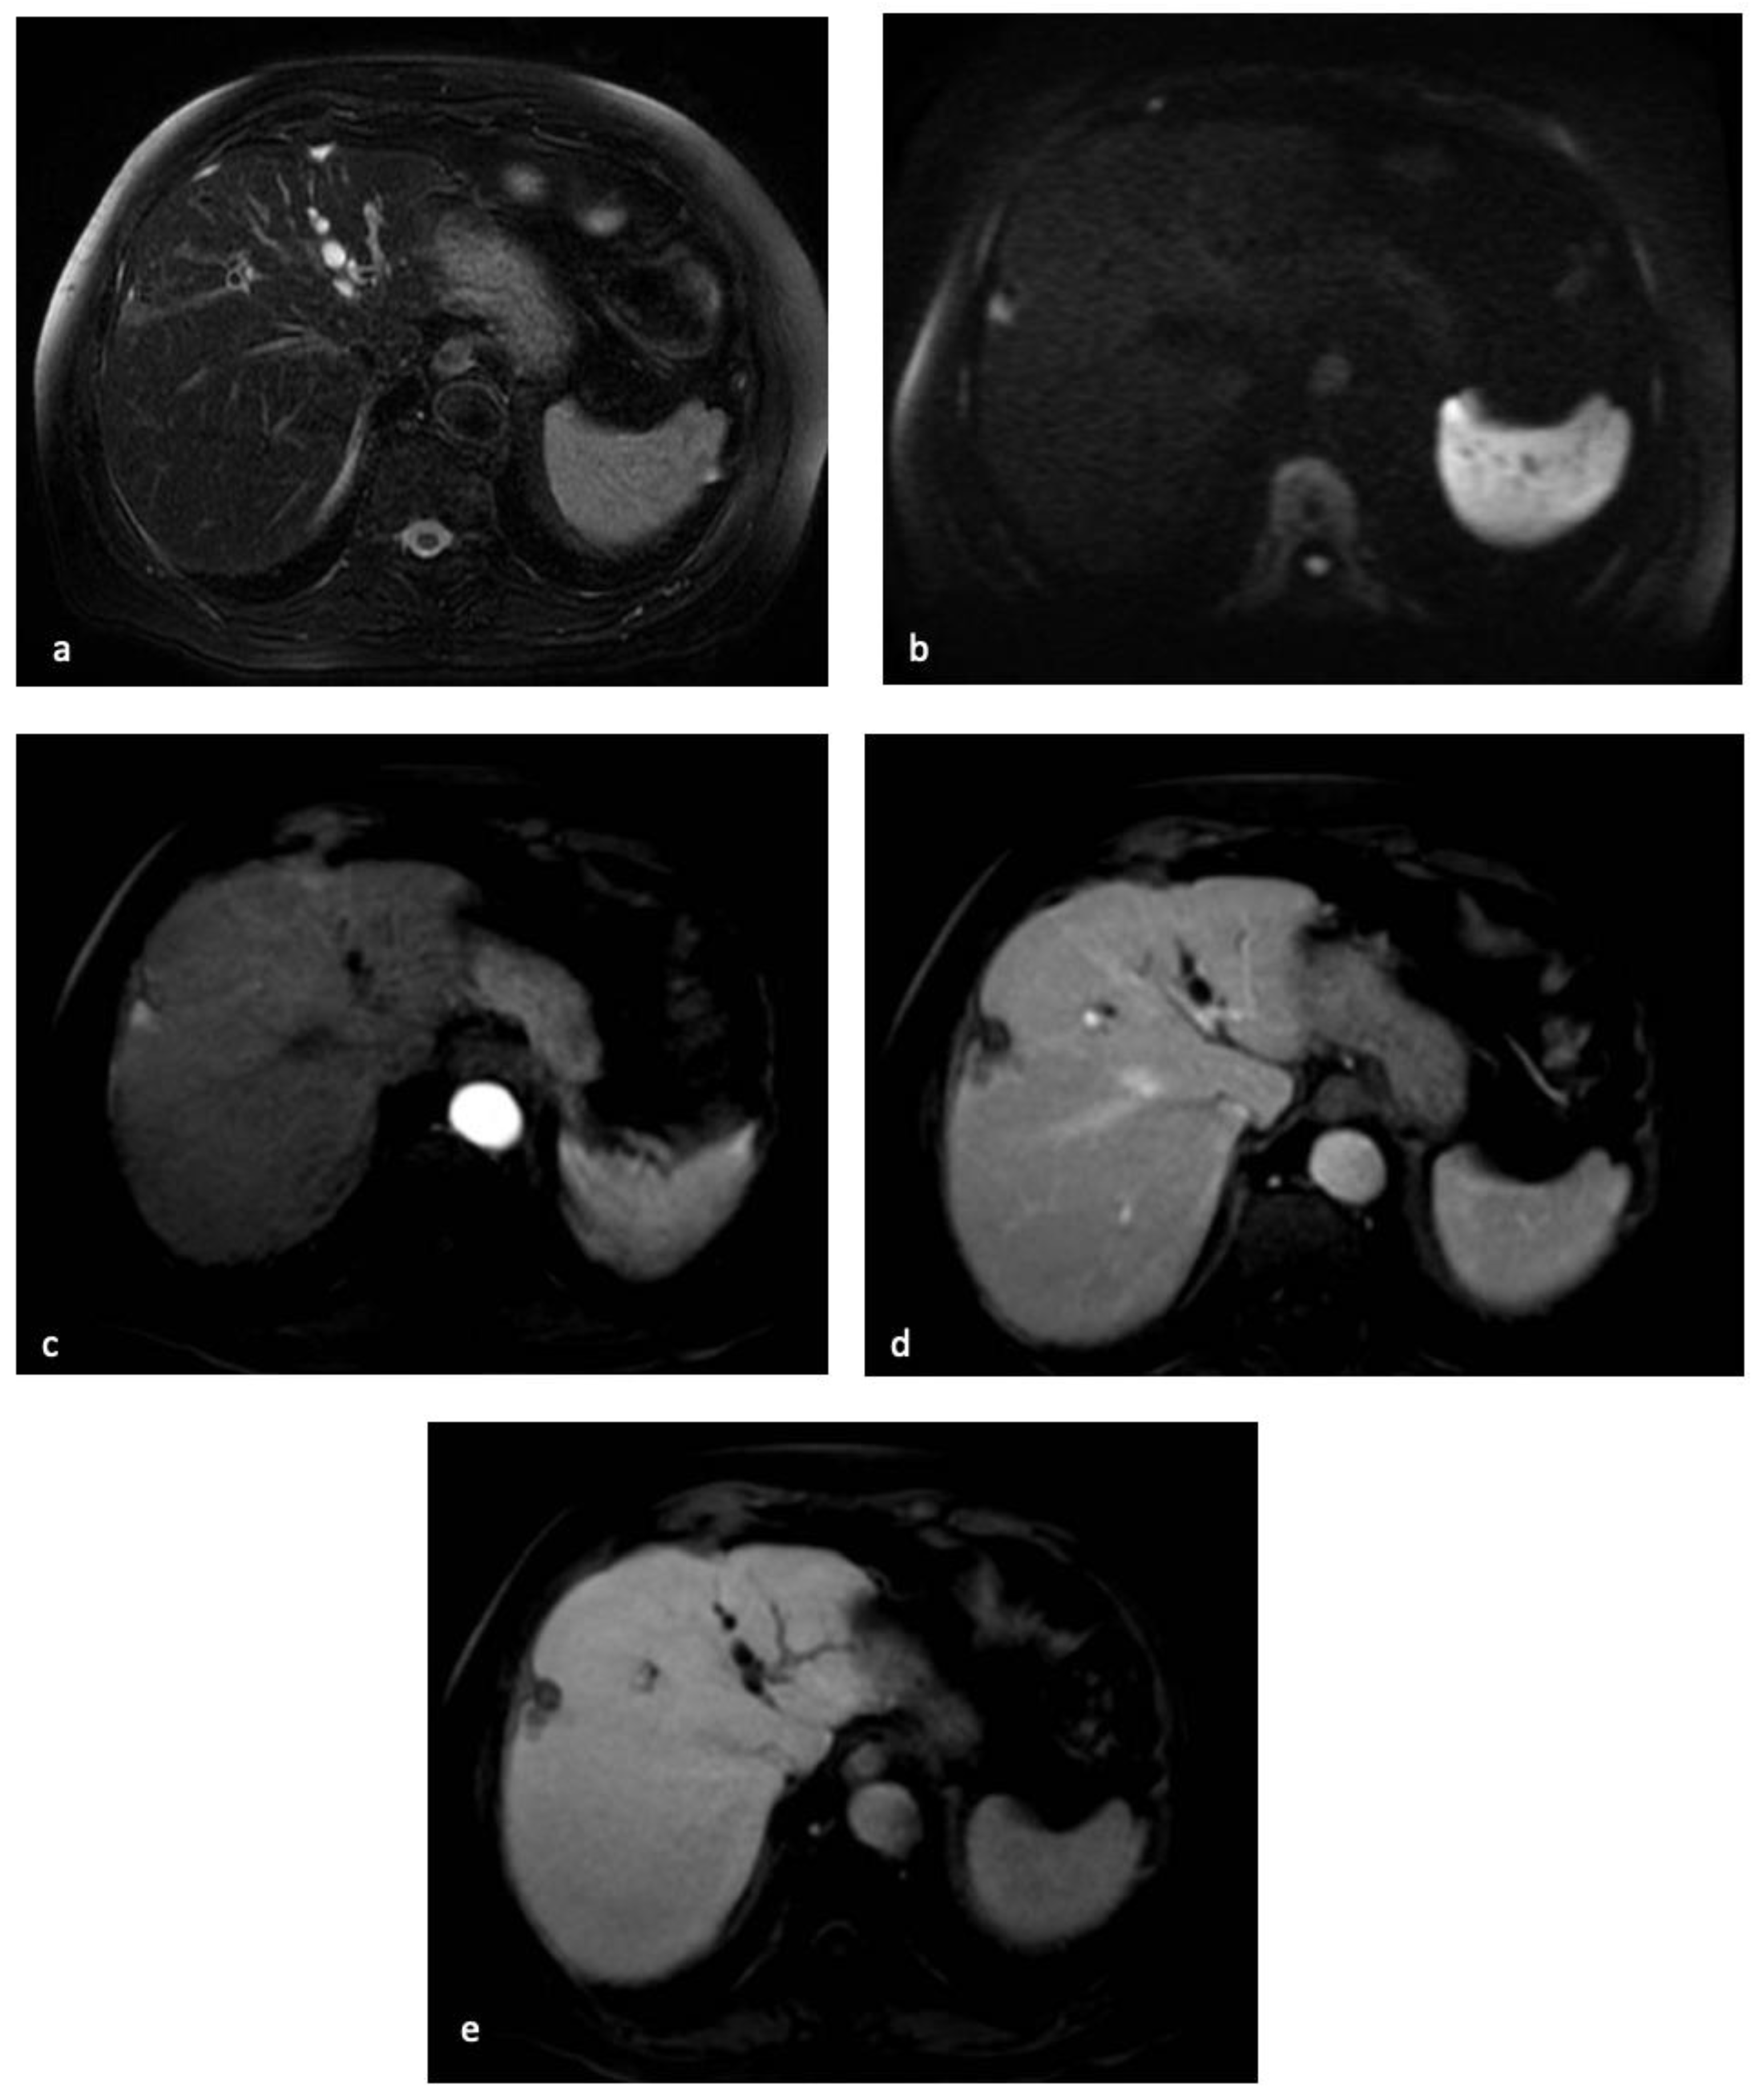

Figure 3.

MR examination of the patient discussed in Figure 1 and Figure 2. On T2-weighted images, the centimetric subcapsular appeared as hyperintense (a). On DWI with a b-value of 1000, the lesion showed signal restriction (b). After administration of a hepatobiliary contrast agent, the lesion showed arterial hyperenhancement (c) with hypointensity in the portal-venous phase (d) and in the hepatobiliary phase. (e) The lesion appeared hypointense.

However, until now, there has been no established consensus regarding the value of HBP hypointensity during liver MRI. In East Asia, some guidelines attribute importance to the use of HBP hypointense appearance, thus permitting the diagnosis of smaller HCCs [88]. Meanwhile, in the Western countries, where liver transplantation is one of the major treatment options [89], the practice guidelines suggest that wash-out should be determined in the portal phase, thus obtaining the highest specificity [12]. In fact, recent studies have suggested that HBP hypointense appearance is highly sensitive and specific for HCC when combining with non-rim APHE [84].